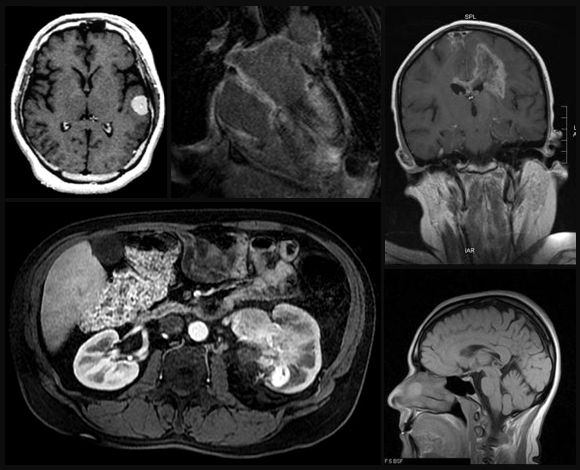

Bone drilling is widely used in many orthopaedic surgery procedures, including those for correcting bone fractures and for joint implantation. Relatively high forces and temperatures experienced during bone drilling can cause significant damage to the bone, such as, and cell death (osteonecrosis). Therefore, a thorough understanding on and predictive thermo-mechanical models for the bone drilling process are needed. The main objective of this research is to develop mechanical and thermal models for the bone drilling process with applications to orthopaedic surgery. A comprehensive investigation including analysis, modeling, and experimentation of thermo-mechanical aspects of bone drilling was performed for the bone drilling process with applications to orthopaedic surgery. The models will enable prediction of drilling forces and temperature distribution in the bone for given drill-bit geometry, drilling conditions, and material characteristics of the bone. The ultimate goal is to improve the outcome of surgical procedures by reducing iatrogenic trauma and invasiveness of the procedure. The oucomes of this research can be applied to robotic surgeries, medical devices, and/or virtual training program for surgeons with applications to surgeries (e.g., orthopaedic surgery, orthodontic srugery, facial surgery, and neurosurgery, etc.).